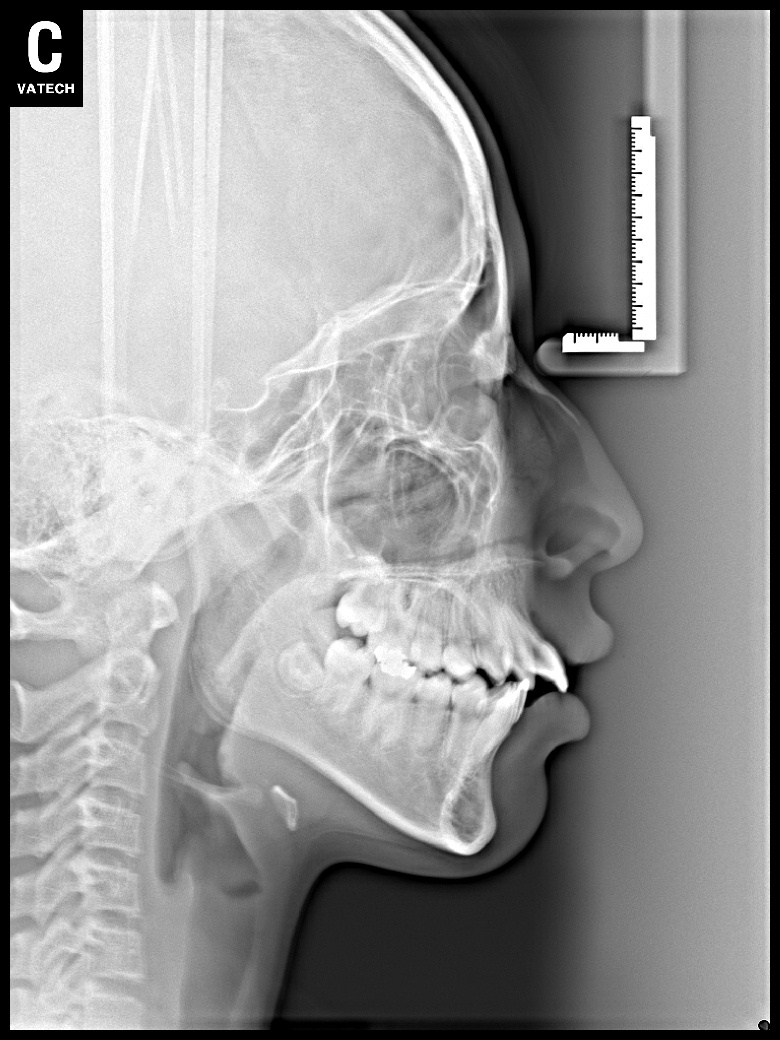

치료 전 사진입니다.

치료 후 사진입니다.